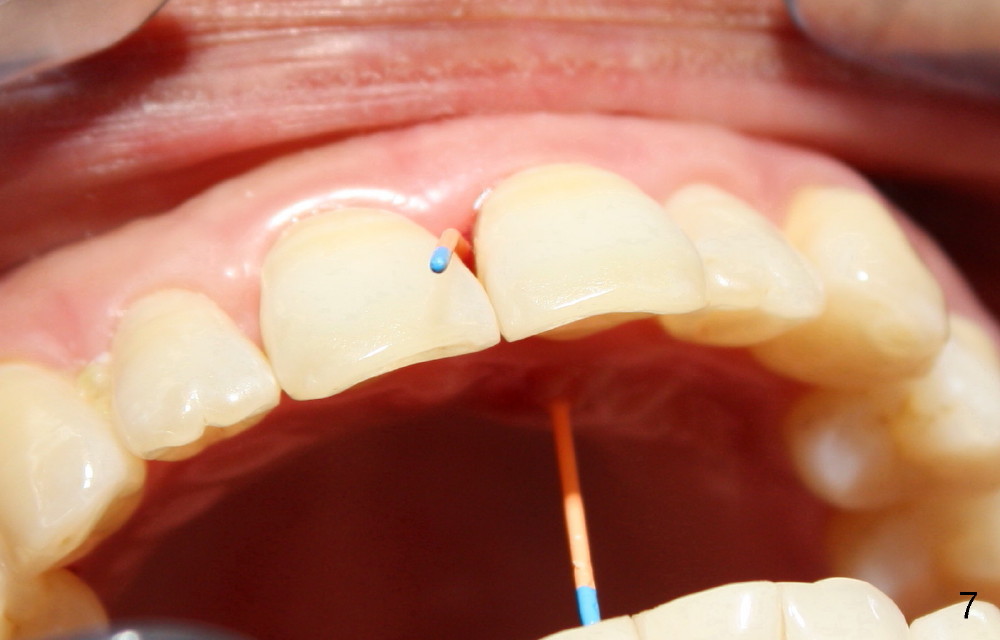

A 60-year-old lady had an abscess mesial to #9 six years ago (Fig.1,2 <), treated as a perio lesion by laser (Fig.3) and osseous surgery without bone graft (Fig.6, followed by CT exam revealing semi-circumferential bone loss (Fig.4,5). When the perio treatment failed, attention was paid to endo aspect (Fig.7-9). In fact the pulp was found to be vital when access to root canal therapy was made. As expected, the treatment failed again. The palatal fistula persisted. The infection was suspected to be a source of remote immediate implant site (#30). The tooth #9 was extracted. It appears that there is a semilunar crack line in the linguomesial root (Fig.12). When the socket healed 2 weeks post extraction (Fig.10), the #30 buccal defect was debrided with bone graft. There was no bone resorption 4 weeks post extraction (Fig.11); a 4.5x17 mm implant was placed (Fig.13-15). An immediate provisional was fabricated (Fig.16-18). Fig.19,20 were taken 3 months post implantation and 7 months post cementation, respectively. Dense bone forms around the implant coronally 4 years 5 months post cementation (Fig.21), while the gingiva is healthy palatally (Fig.22) and buccally (Fig.23).